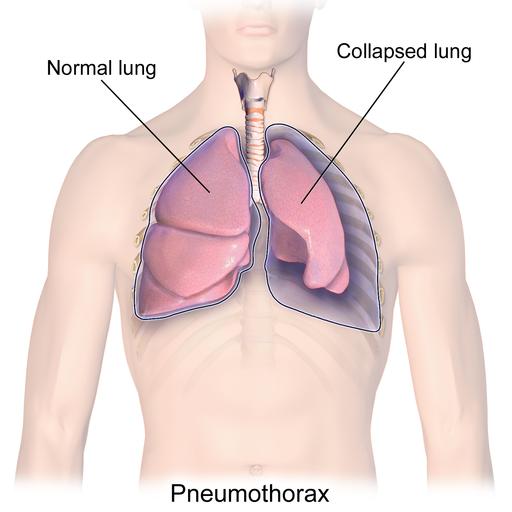

Симптомы и причины скопления воды в легких